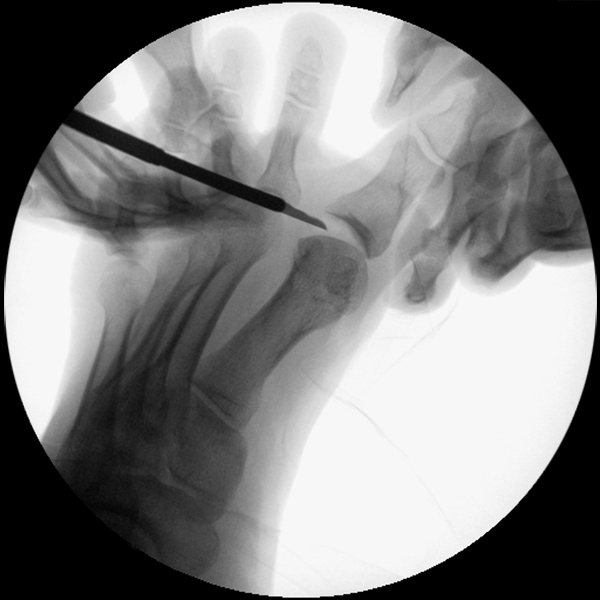

• Positionierung des Bildwandlers: 90° Winkel zum Os metatarsale I. Benötigt wird die Durchleuchtung des Vorfußes a.p., seitlich und schräg.

1. Abtragung der Exostose am Köpfchen des 1. Mittelfußknochens

2. Subcapitale intraartikuläre Osteotomie

3. Laterales Release

4. Akin Osteotomie der Großzehengrundphalanx

Zum Lesen der Bildbeschreibung und zur Vollansicht bitte die Bilder anklicken.